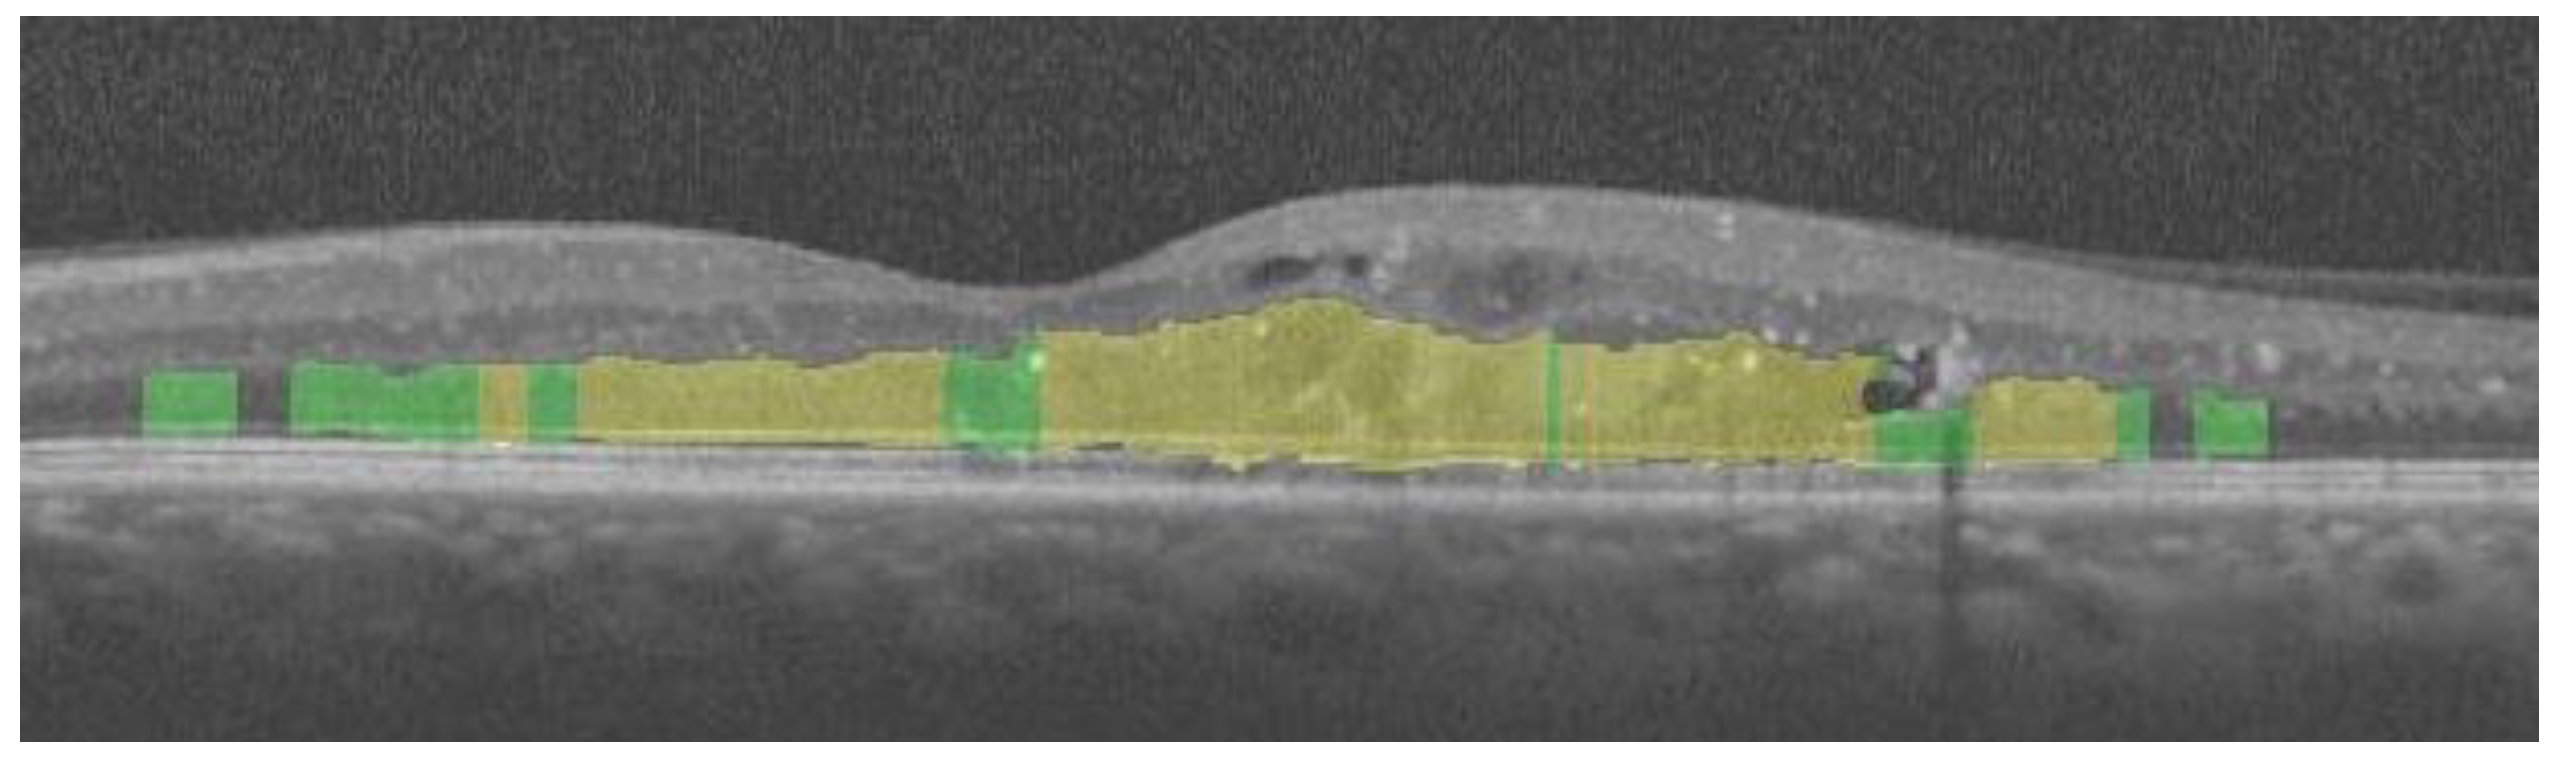

Automatic Identification and Segmentation of Diffuse Retinal Thickening Macular Edemas Using OCT Imaging †

2. Methodology